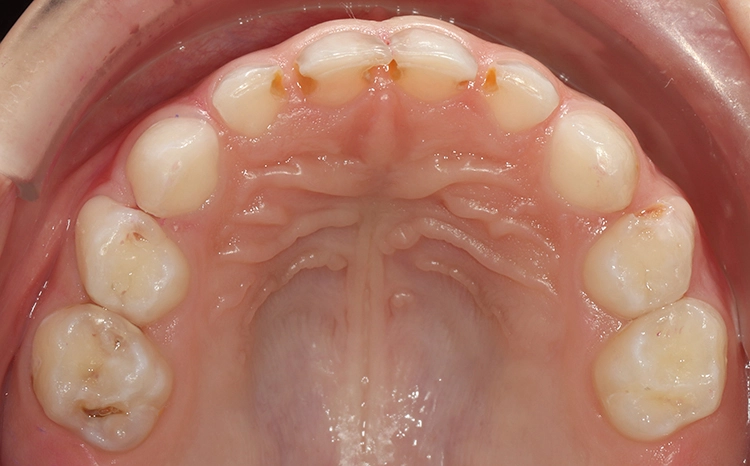

Beim Kleinkind spielt primär die frühkindliche Karies eine Rolle, die initial meist durch kariöse Läsionen an den Oberkieferfrontzähnen gekennzeichnet ist (Abb. 2). Im permanenten Gebiss unterliegen die Kauflächen der durchbrechenden 1. und 2. Molaren insbesondere in der ca. 1,5 Jahre dauernden Durchbruchsphase einem erhöhten Kariesrisiko. Während kieferorthopädischer Maßnahmen mit festsitzenden Apparaturen bei Jugendlichen sollte besonderes Augenmerk auf die Beurteilung der Mundhygiene, wie dem Vorhandensein kariogener Plaque auf Kariesrisikoflächen (Abb. 3), und Kariesaktivität gelegt werden, um frühzeitig präventiv einzugreifen und klinische Bilder mit kariösen Läsionen an fast allen Zähnen möglichst zu vermeiden (Abb. 4).